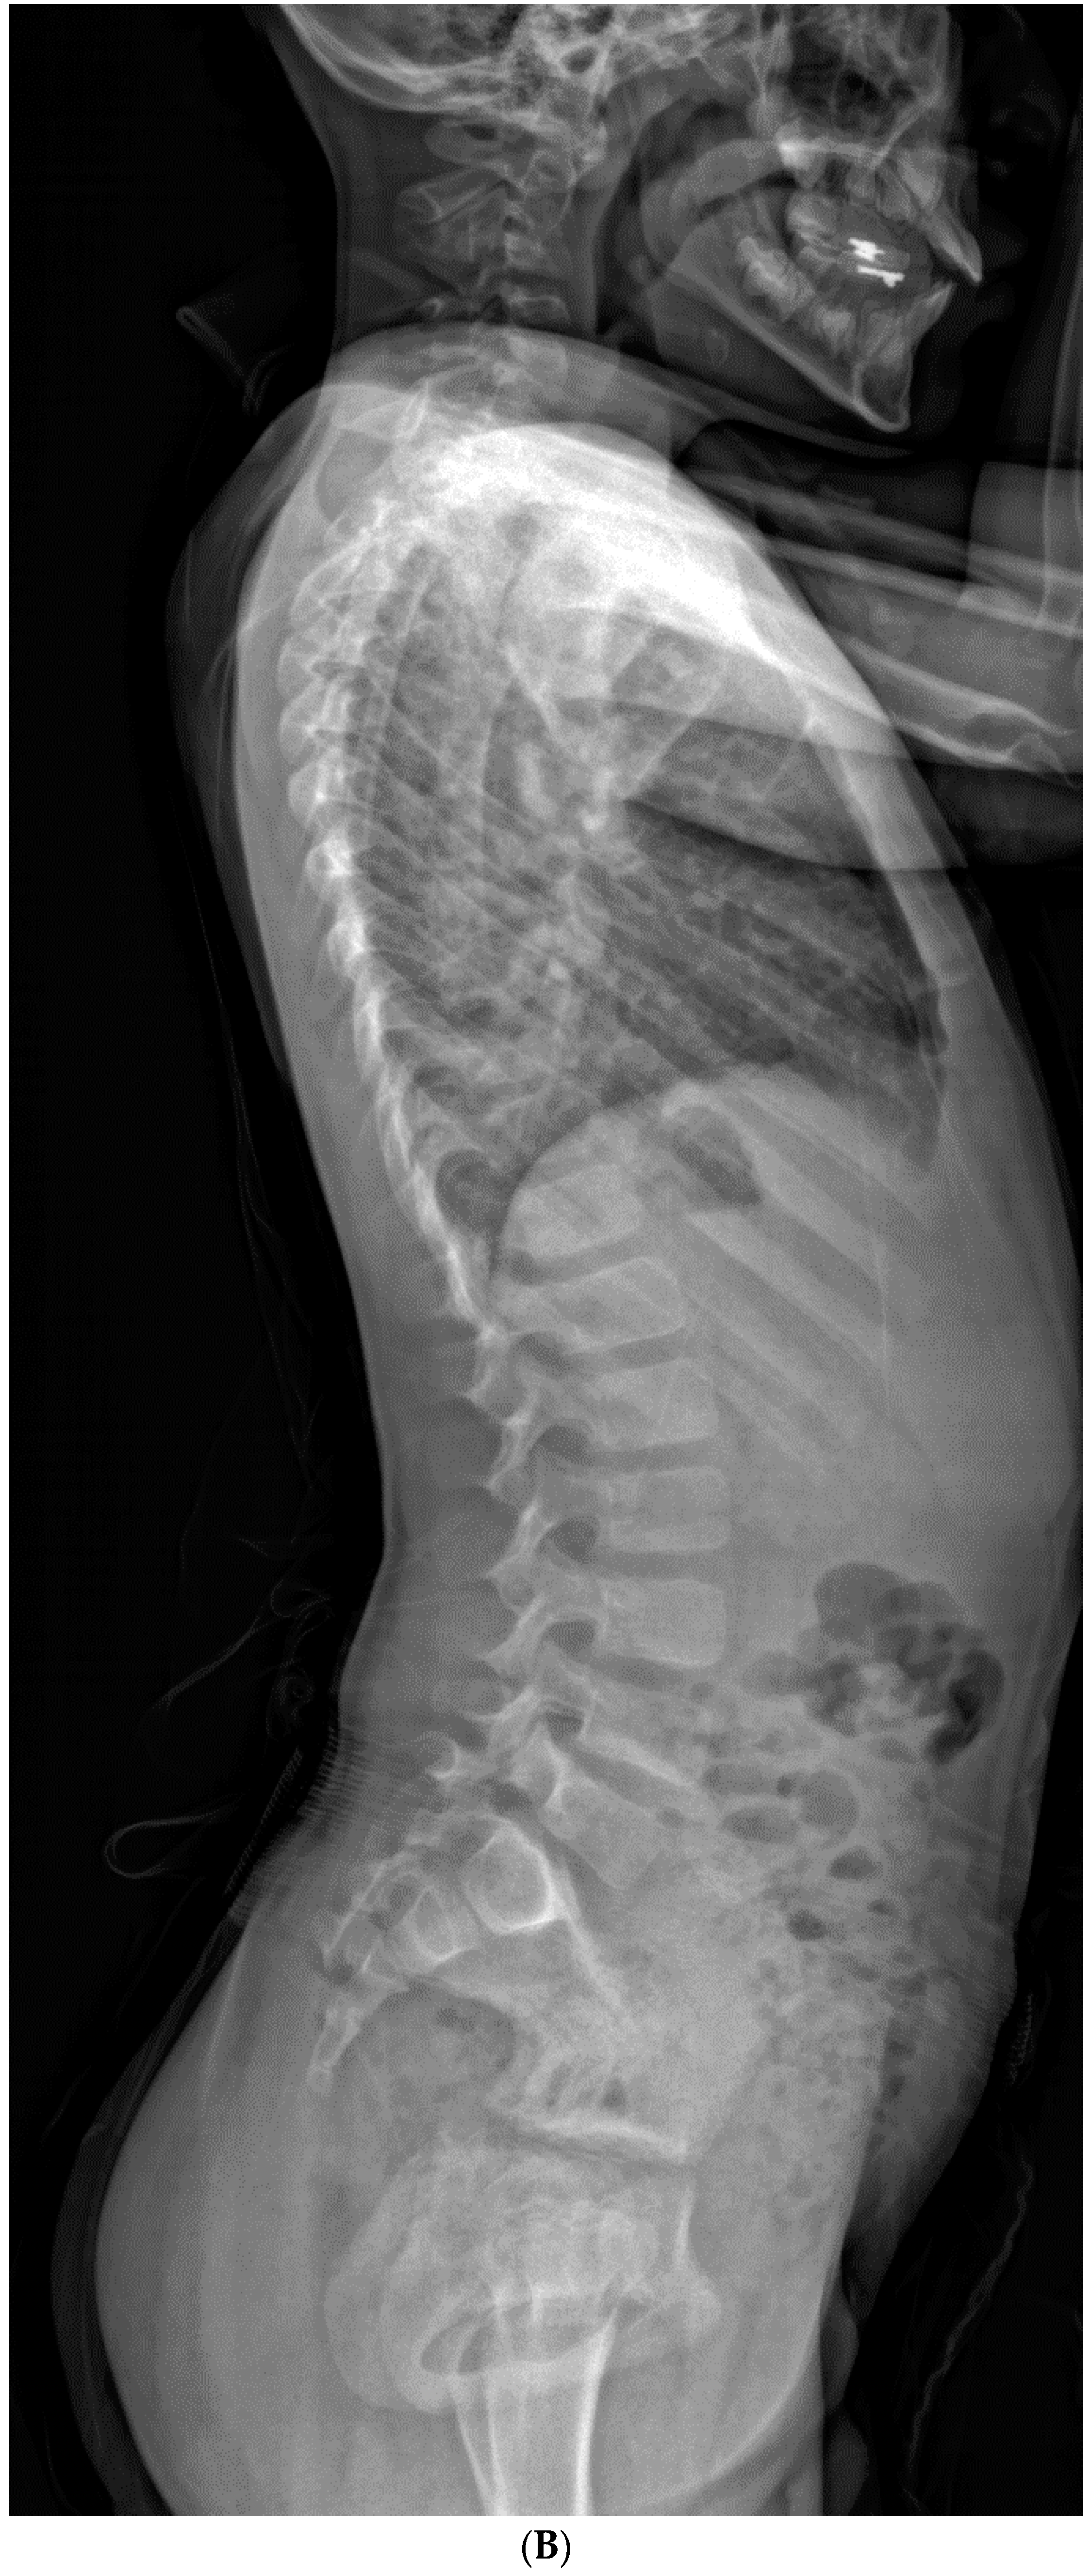

Risk Factors for Progression of Cervical Congenital Scoliosis and Associated Compensatory Curve Behavior

3. Results